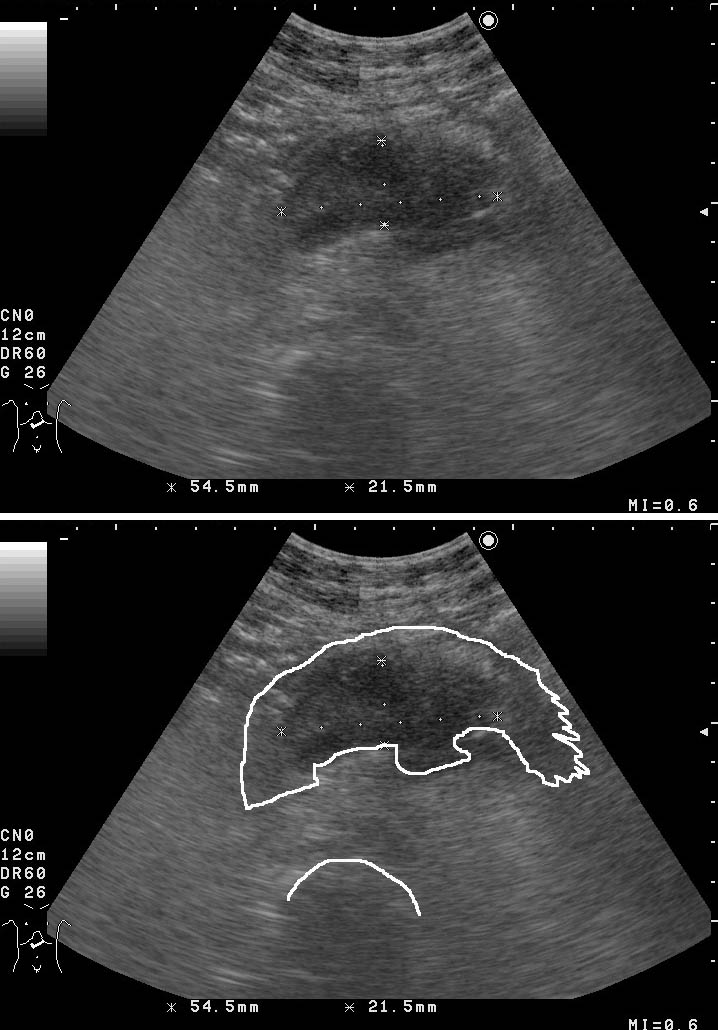

Опухоль тела панкреас. Pancreatic body tumor.

38-летняя женщина с болями в животе с иррадиацией в спину.

На КТ (без контрастирования - 2000 год) патологии не выявлено.